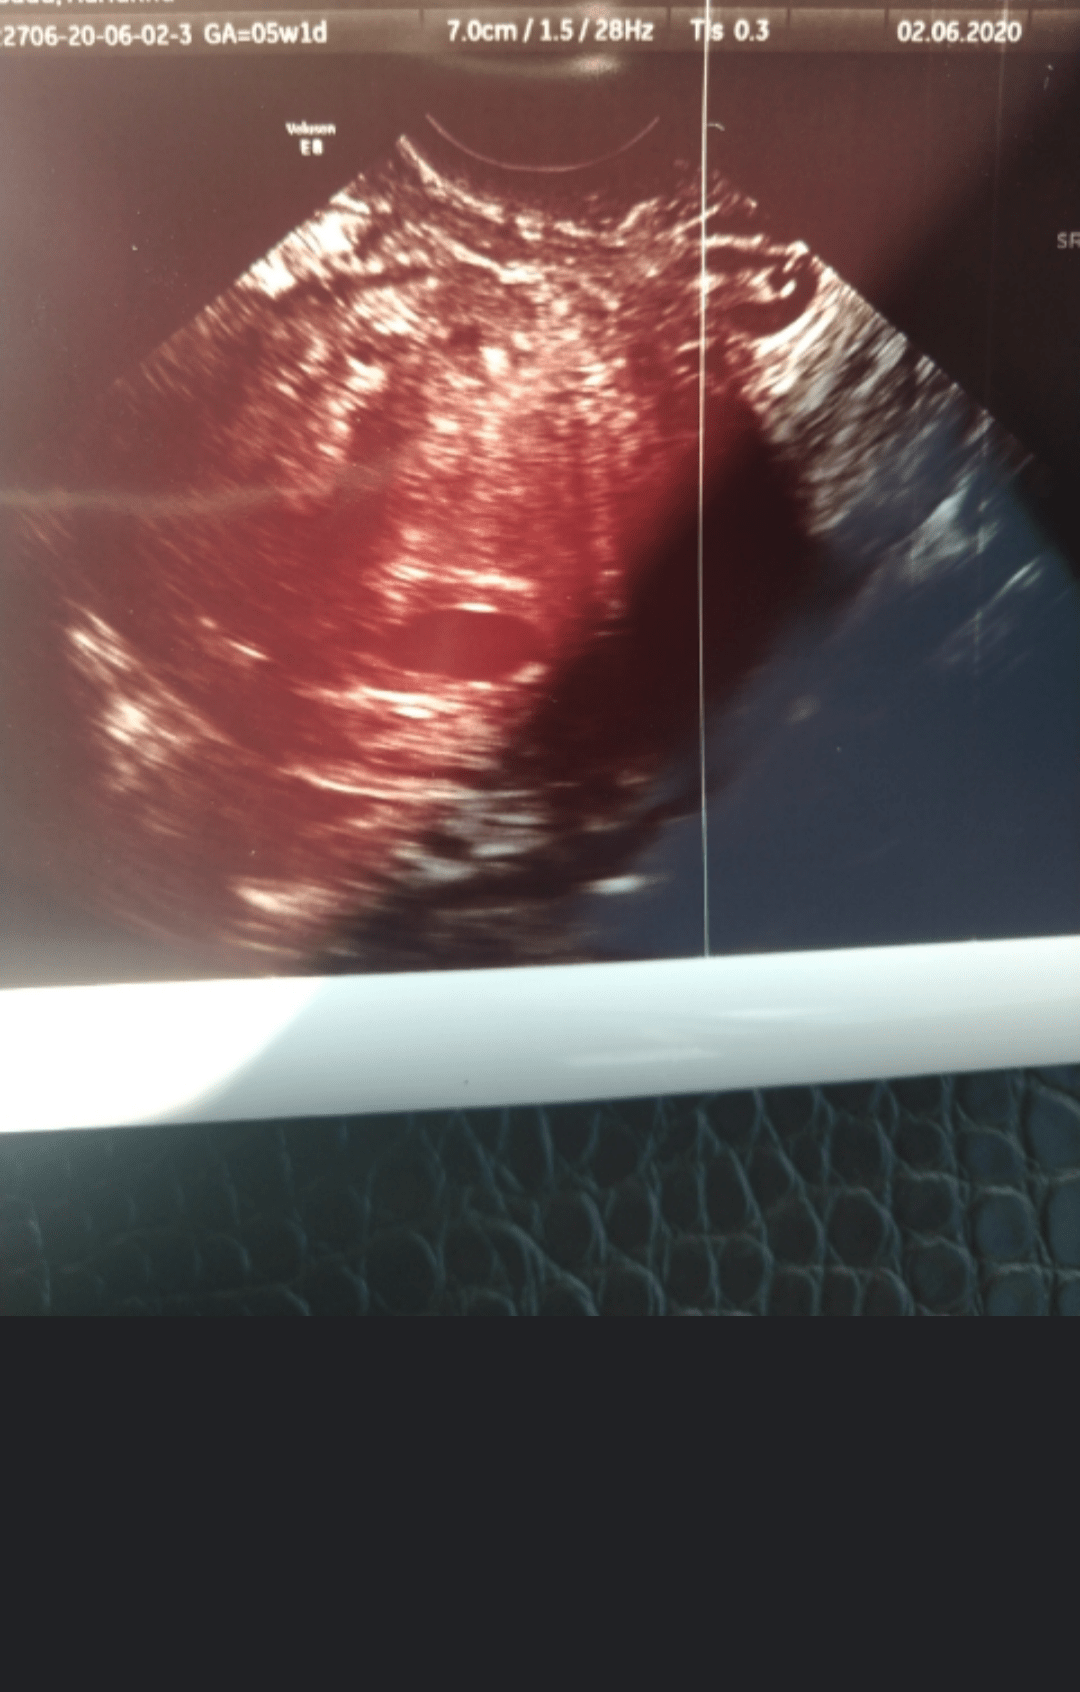

Mój kropek w 5+1 wyglądał tak, też słabo było widać, właściwie nic 🤣 no i to było na drugie dzień po becie 13 tys, więc była już o wiele większą a na usg nadal dupa, więc różnie to bywa z tą betą i obrazem USG.

• Screenshot_20201019-140223~2.png

Screenshot_20201019-140223~2.png